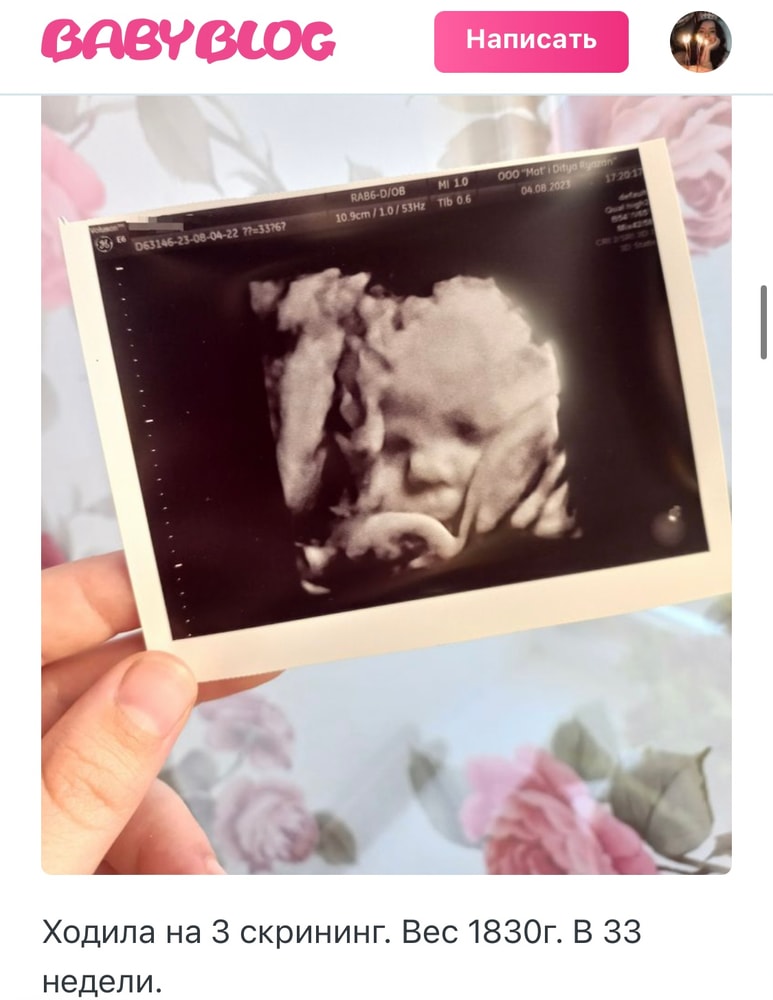

Самый красивые фотки у меня получились в 33 недели.

Дарья, поделитесь, если не тайна😍

Веточка, вот вам разница 33 и 20 недель. Ничего не поздно. Изображение Изображение В 20 недель там уродец худенький 😁